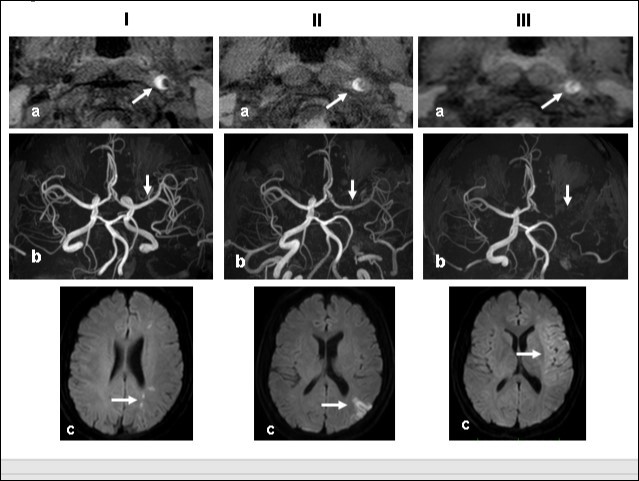

This 43-year-old Japanese male presented with right hand dysesthesia. He has not recognized his neck pain and Horner’s syndrome( oculosympathetic palsy). Magnetic resonance imaging(MRI) performed on a 3T TX scanner (Philips Achieva, The Netherlands) demonstrated dissection of the left cervical carotid artery (CCA; Figure 1A,1B ); no ischemic area was detected in the left cerebral brain. Axial section views of the CCA segment revealed a typical crescent hematoma; a bright, hyper-intense circle representing the narrowed arterial lumen was visualized. A T1-volumetric isotropic turbo spin echo acquisition (VISTA) sequence resulted in the diagnosis of dissection of the CS-ICA (Figure 1C). He had no conventional stroke risk factors such as hypertension, diabetes, hyperlipidemia, a history of cardiac valvular disease, arterial fibrillation, or features of inherited connective tissue disorder. Also absent was a history of arterial trauma and we were unable to identify any etiological factor(s). One week later he developed Gerstman symptoms; border zone ischemia was observed in the left cerebrum (Figure 2-Ic). He was admitted and the administration of antiplatelet agents was started. The left middle cerebral artery (MCA) was supplied via antegrade circulation (Figure 2-Ib) and an increase in the flow-void intensity was noted (compare Figure 1C with Figure 2-Ia). MRI studies acquired one week later revealed spreading of the ischemic area to beyond the watershed zone between the left anterior cerebral artery (ACA) and the MCA, and the MCA and the posterior cerebral artery (PCA) (Figure 2-IIc). The area of dissection had spread from the ICA bifurcation to the top of the ICA. The blood supply to the left MCA territory derived from the circle of Willis (Figure 2-IIb). The flow-void intensity had increased further (compare Figure 2-Ia with Figure 2-IIa). Two weeks after his admission he suddenly experienced complete right-sided hemiparesis with motor aphasia. MRI performed within 45 min demonstrated diffuse ischemia in the left MCA territory (Figure 2-IIIc), the left A1 segment could not be visualized. The left MCA and its A1 segment were completely occluded (Figure 2- IIIb). The flow-void intensity indicated complete occlusion of the true lumen (Figure 2-IIIa). He underwent emergency left superficial temporal artery (STA)-MCA bypass surgery within 6 hours; double anastomosis was successful. External decompression was performed to prevent neurological deterioration due to severe brain swelling. An intensive rehabilitation has been continued for him after operation. His functional independence measure (FIM) score recorded over the course of 4 months showed remarkable improvement ( Figure 3) as did the standard language test for aphasia.

Figure 2.Time course Columns I, II, and III are images obtained 1, 2, and 3 weeks, respectively, after the start of dissection of the cervical segment of the internal carotid artery. Ia, IIa, IIIa.T1 VISTA images of the same segment shown in Fig. 1C. The dark area reflective of the low void progresses to hyperintensity by week 3. IIIa shows complete occlusion of the true lumen by the intramural hematoma (arrow ). Ib, IIb, IIIb. TOF-MRA images of the intracranial arteries. (a) The left MCA is supplied via antegrade flow from the left carotid artery (arrow). (b) Flow from the left carotid artery disappeared from the ICA bifurcation to the top of the ICA. Blood supply to the left MCA derives from the circle of Willis via the anterior- or the posterior communicating artery (arrows). By week 3, flow to the left MCA, even via the left A1 segment of the anterior cerebral artery had disappeared completely. Ic, IIc, IIIc. Diffusion-weighted images at the basal ganglia level. Week 1: a few hyperintense areas are visualized in the border zone of the left cerebrum (arrow). Week 2: Note the hyperintensity area in the watershed zone between the left ACA and the MCA, and between he MCA and the PCA (arrow). The image acquired on week 3 shows a diffuse hyperintensity area in the left MCA territory (arrow).

Time course Columns I, II, and III are images obtained 1, 2, and 3 weeks, respectively, after the start of dissection of the cervical segment of the internal carotid artery. Ia, IIa, IIIa.T1 VISTA images of the same segment shown in Fig. 1C. The dark area reflective of the low void progresses to hyperintensity by week 3. IIIa shows complete occlusion of the true lumen by the intramural hematoma (arrow ). Ib, IIb, IIIb.  TOF-MRA images of the intracranial arteries. (a) The left MCA is supplied via antegrade flow from the left carotid artery (arrow). (b) Flow from the left carotid artery disappeared from the ICA bifurcation to the top of the ICA. Blood supply to the left MCA derives from the circle of Willis via the anterior- or the posterior communicating artery (arrows). By week 3, flow to the left MCA, even via the left A1 segment of the anterior cerebral artery had disappeared completely. Ic, IIc, IIIc.  Diffusion-weighted images at the basal ganglia level. Week 1: a few hyperintense areas are visualized in the border zone of the left cerebrum (arrow). Week 2: Note the hyperintensity area in the watershed zone between the left ACA and the MCA, and between he MCA and the PCA (arrow). The image acquired on week 3 shows a diffuse hyperintensity area in the left MCA territory (arrow).